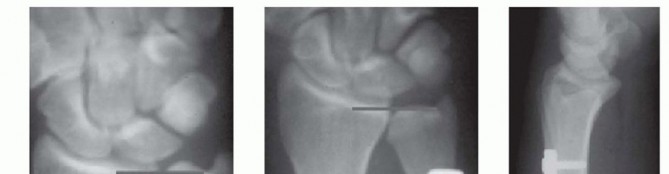

TECH FIG 5 • A. Posteroanterior (PA) wrist radiograph showing ulnar positive variance. B,C. PA and lateral radiographs after ulnar shortening osteotomy. The interfragmentary lag screw compresses the osteotomy site.